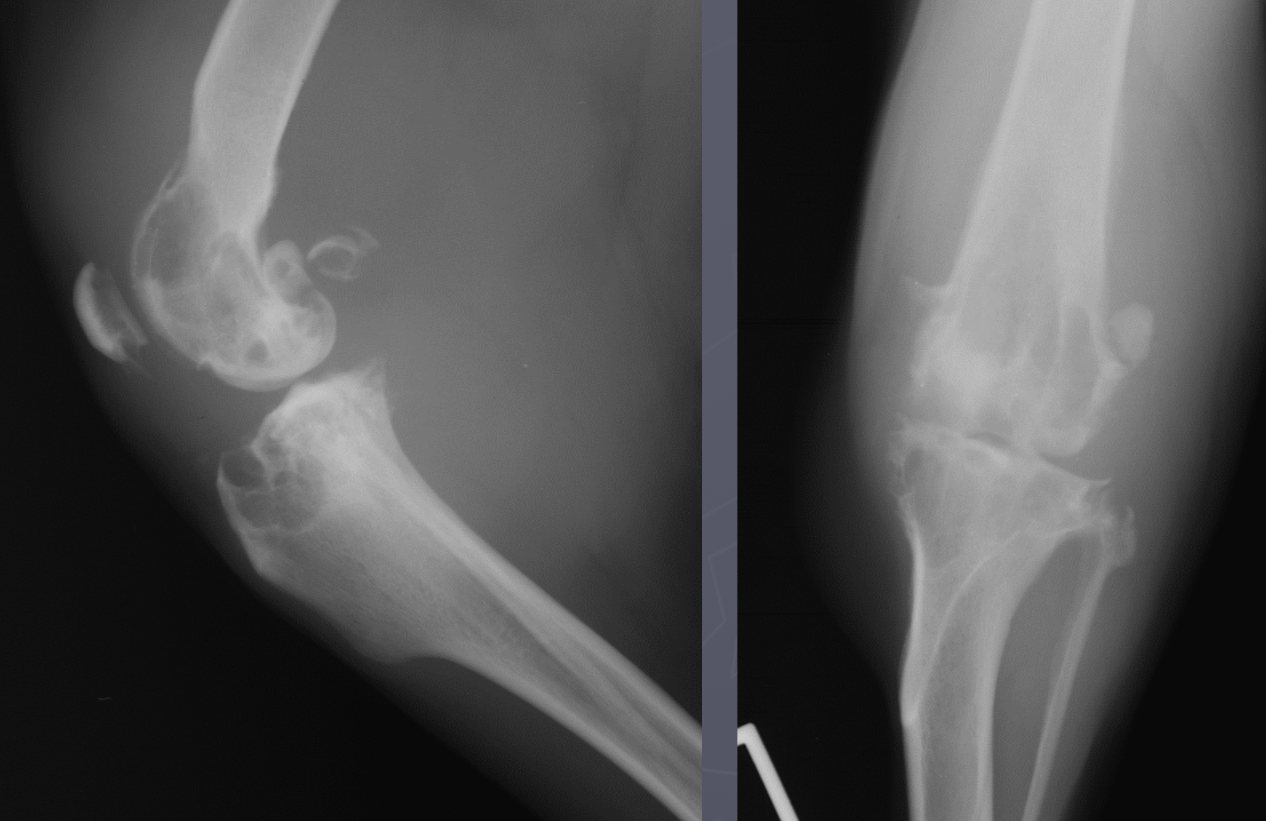

which OCD lesions are these in the dog

A = cd humerus

B = medial humeral condyle (elbow)

C = medial trochlear ridge (ankle)

D =lateral femoral condyle (knee)

Dog OCD signalment

young giant breed (6-9 mo age)